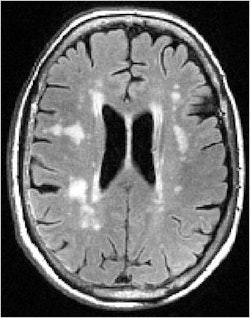

White-matter hyperintensities are commonly seen on MRI of elderly subjects. Image courtesy of Dr. Lisa Silbert.

"With older individuals, we very commonly see these lesions," Silbert said. "They are often called white-matter hyperintensities because they are bright on certain MR images. These white-matter lesions can affect how we think, walk, and move as we grow older."